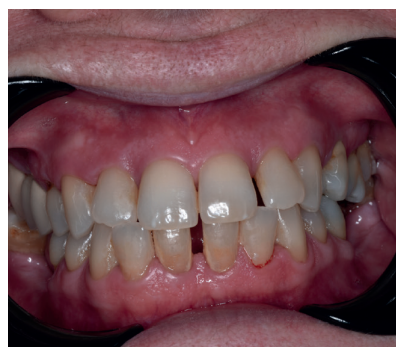

Caso clínico: Se presenta el caso clínico de una paciente con hipertensión, diabetes tipo II, hipotiroidismo, depresión, obesidad y déficit de vitamina D. Se hace una revisión de la actuación del odontólogo en la clínica cuando se presentan pacientes con dichos cuadros y las consideraciones a tener en cuenta con respecto a la prescripción y administración de medicación. El objetivo es presentar recomendaciones de tratamiento a partir de un caso clínico de una paciente con varias afecciones sistémicas en la que se realiza un tratamiento multidisciplinar. Para eso se ha realizado una revisión narrativa que se considera útil para la actividad clínica diaria

Clinical case: The clinical case of a patient with hypertension, type II diabetes, hypothyroidism, depression, obesity and vit D deficiency is presented. A review is made of the performance of the dentist in the clinic when patients with these conditions appear and the considerations to take into account with respect to the prescription and administration of medication. The objective is to present treatment recommendations based on a clinical case of a patient with several systemic conditions in which a multidisciplinary treatment is carried out. For this, a narrative review has been carried out that is considered useful for daily clinical activity.